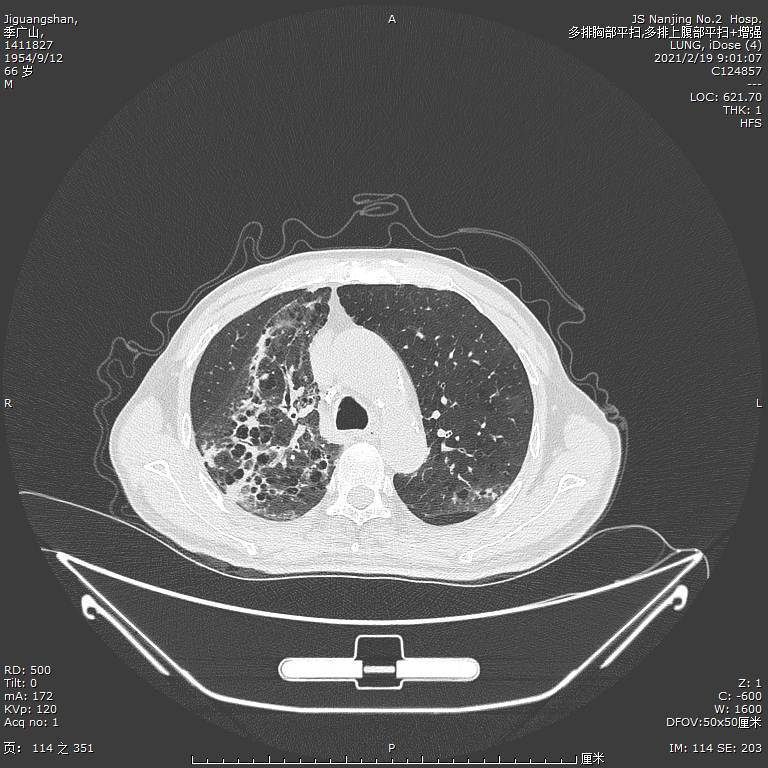

入院第六天我们通过 mNGS 检测出患者的血液和痰液中存在羊流产衣原体,可确认为肺炎的病原体但是由于衣原体感染大多都是混合感染,因此我们并没有停止帕拉西林钠他唑巴坦钠的使用在治疗第 10 天,我们复查了胸部 CT,结果示两肺间质性炎症较前改善,两肺少量胸腔积液(图 2)。

图 2:入院第十天胸部 CT,两肺间质性炎症较前改善,两肺少量胸腔积液患者因为检测出了乙肝小三阳和梅毒特异性抗体阳性,因此患者转院前往传染病医院进一步治疗,嘱患者出院后口服莫西沙星和克拉霉素抗感染治疗我们在患者出院二十天后进行随访。